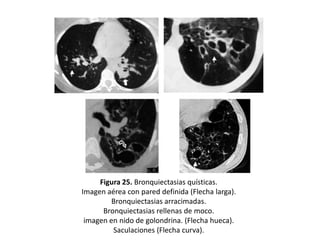

• Quísticas:

– Es la expresión más grave de la enfermedad.

– Los bronquios adquieren una forma sacular o de

quiste.

– Pueden presentar niveles hidroaéreos o estar

agrupadas en racimos o hileras.

– Adoptan la típica imagen de “nido de golondrina”

cuando el moco se acumula dentro de las lesiones y

aparece un nivel hidroaéreo (Figuras 11, 14, 15, 17, 21

y 25).

– Son frecuentes en la aspergilosis broncopulmonar

alérgica (ABPA) y en la fibrosis quística

Figura 25. Bronquiectasias quísticas.

Imagen aérea con pared definida (Flecha larga).

Bronquiectasias arracimadas.

Bronquiectasias rellenas de moco.

imagen en nido de golondrina. (Flecha hueca).

Saculaciones (Flecha curva).